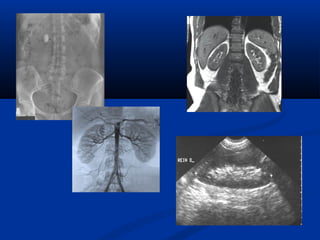

Khaûo saùt sieâu aâmKhaûo saùt sieâu aâm